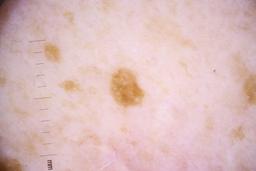

ISIC_4077341

- Challenge 2020: Training

- IP_1969685 IL_9238622

Clinical

| Field | Value |

|---|---|

| acquisition_day | 1 |

| age_approx | 50 |

| anatom_site_1 | Trunk |

| anatom_site_2 | Anterior trunk |

| concomitant_biopsy | False |

| dermoscopic_type | contact non-polarized |

| diagnosis_1 | Benign |

| diagnosis_confirm_type | serial imaging showing no change |

| family_hx_mm | False |

| image_type | dermoscopic |

| lesion_id | IL_9238622 |

| patient_id | IP_1969685 |

| personal_hx_mm | True |

| sex | male |